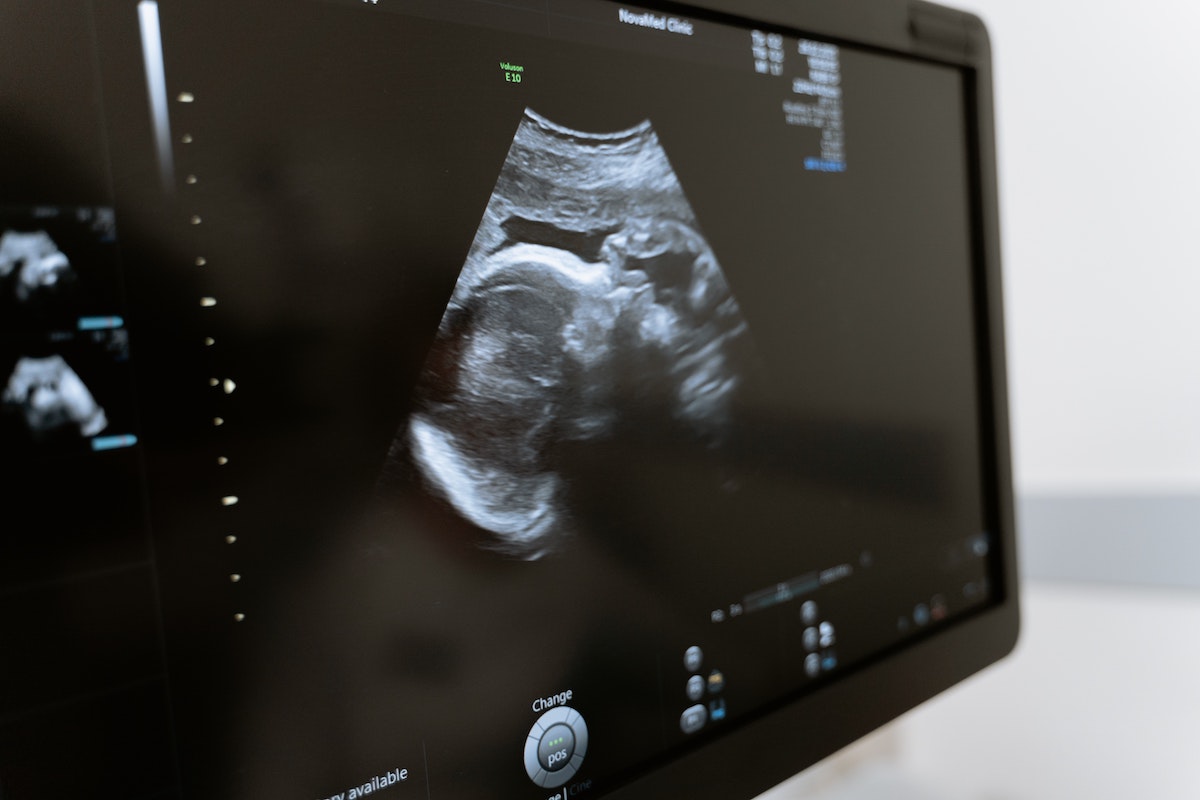

Pregnancy is such an exciting time for any expectant parent. One of the most exciting moments is going for an ultrasound when you finally get that first glimpse at your bundle of joy. As your baby grows, you’ll an ultrasound will allow you to see your baby as it develops. You may begin to notice facial features or even see your little one already sucking on their thumb or blowing bubbles. Those tiny feet kicking you? They’ll start to appear, too.

It’s amazing how quickly (but slowly) these soon-to-be humans develop. Your 8-week ultrasound may show a small blob-like photo, whereas an ultrasound done just a few weeks later will reveal a forming head and even cheekbones. As you progress in your pregnancy, you’ll see more and more development.

However, ultrasounds are also a chance for doctors to ensure the future little one is developing as they should. You already love your growing baby, and naturally, want to hear everything is smooth sailing. Learning more about what you’ll see and what a doctor looks for can help you feel informed and empowered during your pregnancy. Here’s what to know about ultrasounds.

Also known as the anatomy scan, the 20-week ultrasound is a highlight for many pregnant people and their partners (if applicable). This second-trimester scan is the longest. You’ll get a true inside look at your baby-to-be. The tech will point out their developing organs, like the heart and kidneys.